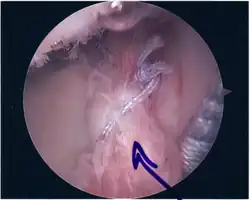

Surgical treatment of SLAP tears has become more common in recent years. The success rate for repairing isolated SLAP tears is reported between 74-94%.[10] While surgery can be performed as a traditional open procedure, an arthroscopic technique[11] is currently favored being less intrusive with low chance of iatrogenic infection.[12]

Procedure

Following inspection and determination of the extent of injury, the basic labrum repair is as follows.

- The glenoid and labrum are roughened to increase contact surface area and promote re-growth.

- Locations for the bone anchors are selected based on number and severity of tear. A severe tear involving both SLAP and Bankart lesions may require seven anchors. Simple tears may only require one.

- The glenoid is drilled for the anchor implantation.

- Anchors are inserted in the glenoid.

- The suture component of the implant is tied through the labrum and knotted such that the labrum is in tight contact with the glenoid surface.